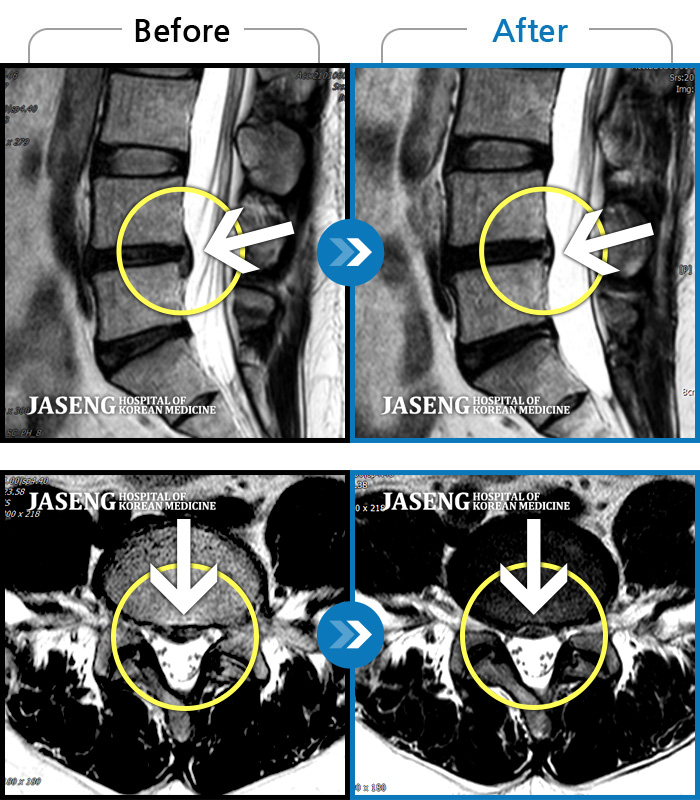

MRI로 보는 치료사례

허리디스크

많이 본 사례

강남 · 이남우 원장

허리 통증과 함께 발끝 저림이 1년 이상 되었으며 최근 1-2개월 사이에 증상이 급격히 심해져 우측 다리 앞 뒤가 당기고 힘이 빠져 본원에 내원함

촬영시기

2023.11.20 ~ 2024.08.12

2024.12.24

조회수 688